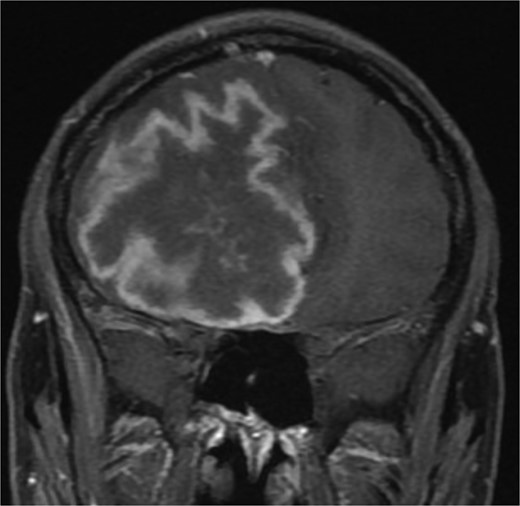

(A and B) Brain MRI with contrast showing signs of intracranial abscess in the left side with mass effect and midline shift to the right side.

A previously healthy 36-year-old man presented to the emergency department complaining of persistent frontal headache, dizziness, and vomiting of 1 month duration, with no history of orbital complaints (e.g. visual deficits or swelling) or neurological deficits (e.g. limb weakness or seizure-like movements). On examination, the nasal endoscopy showed dry crusts filling the right nasal area. Therefore, due to the subtle symptoms’ origin, the patient was admitted, and a computed tomography (CT) scan of the head and a magnetic resonance imaging (MRI) of the brain were scheduled. The head CT scan revealed complete opacification of the maxillary, ethmoid, frontal, and sphenoid sinuses with bone destruction affecting the left lamina papyracea and roof of the ethmoid air cells (Fig. 1A). The brain MRI demonstrated similar findings with intra-orbital extension resulting in left global proptosis, which triggered concerns regarding fungal rhinosinusitis (Fig. 1B). Accordingly, the patient underwent functional endoscopic sinus surgery (FESS) with a right frontal craniotomy and partial removal of the infected brain tissue on the fourth day of his presentation. Specimens from both surgical sites were sent for pathology and cultures during the surgery. The histopathological results confirmed the diagnosis of CGIFRS, and A. flavus was found in the tissue culture. Postoperatively, the patient was stable, and intravenous antifungal treatment (amphotericin B and voriconazole) and high-dose steroid administration (dexamethasone) were started promptly following confirmation of CGIFRS via pathology. One week after the surgery, the patient’s condition suddenly deteriorated: he had a right fixed dilated pupil and spikes of fever. An urgent brain MRI with contrast was performed, which showed an intracranial abscess, and a significant midline shift to the right side (Fig. 2A and B). The patient, therefore, had a right decompression craniotomy and remained intubated and ventilated in the intensive care unit to receive the maximum medical therapy. However, despite this intensive treatment, the patient’s condition continued to worsen, and he ultimately died after 2 weeks.